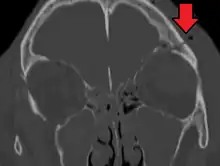

![]() | |

| A subtle temporal bone fracture as seen on CT in a person with a severe head injury | |